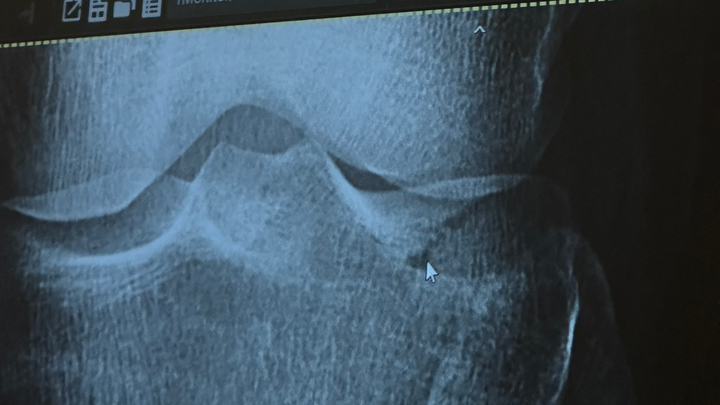

On July 28th, 2025, our beloved friend Xochi was seriously injured during Muay Thai training. She suffered a tibial plateau fracture and a torn MCL — painful injuries that require extensive recovery.